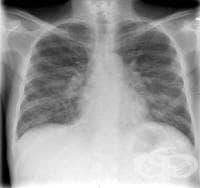

В повечето случаи рентгеновите снимки са необходими, но от пациента зависи да постави под съмнение ц...

Повечето хора имат бегла представа за всички рутинни медицински изследвания, които е необходимо да с...